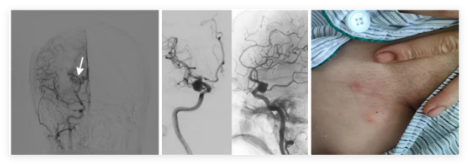

1.脑血管介入诊疗

①手术方法:通过导管将栓塞材料闭塞畸形血管/置入支架改善血供,达到治疗目的。

②适应症:脑动脉瘤、脑动静脉畸形、颈动脉狭窄等。

③手术优势:手术创伤小、恢复快、定位准确、并发症少。